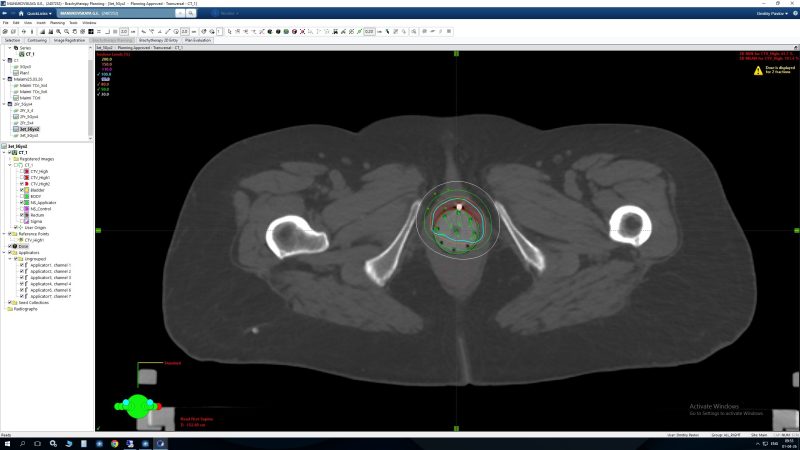

- Еще одной уникальной возможностью брахитерапии является использование ее при лечении рецидивов заболевания или метастатических поражений. Использование многоканального аппликатора позволяет не использовать каналы, которые прилегают к органам риска, что дает возможность максимально снизить дозу на них и уменьшить вероятность побочных эффектов даже при повторном облучении данной области.

Использование всех доступных каналов Исключение каналов, прилегающих к прямой кишке